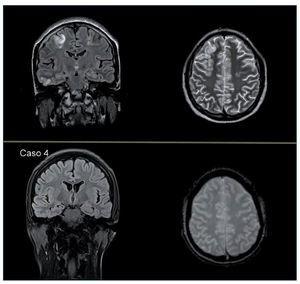

Se realizó una RMNC, que evidenció la presencia de múltiples lesiones, predominantemente de la sustancia blanca subcortical, yuxtacortical y algunas con afectación cortical de localización globalmente simétrica en ambos hemisferios cerebrales y cerebelosas sin restricción de la difusión, compatibles con fenómenos de desmielinización tipo SEPR (figura 2 superior).

Figura 2. Superior: Presencia de múltiples lesiones que afectan a la sustancia blanca subcortical y yuxtacortical y cierta afectación cortical. Se localizan en ambos hemisferios cerebrales, de forma globalmente simétrica, aunque hay áreas de mayor afectación unilateral. Hay lesiones bilaterales y simétricas en ambos hemisferios cerebelosos y a nivel temporobasal, aunque de predominio derecho; también hay afectación parietooccipital bilateral y frontal de predominio derecho, y hay lesiones bilaterales y simétricas en ambas caras mediales de los lóbulos parietales. Se observa una pequeña alteración focal de la señal a nivel profundo localizada en el margen posterior protuberancial a la altura del pedúnculo cerebeloso superior. Inferior: Práctica resolución de las sutiles lesiones hiperintensas córtico-subcorticales bihemisféricas bilaterales supratentoriales.

La RMNC de control a los 2 meses denotó la práctica resolución de las lesiones cerebrales (figura 2 inferior).